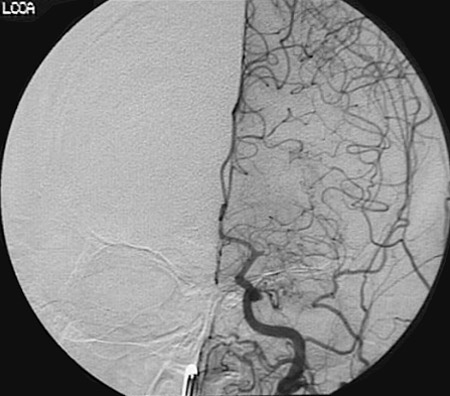

This angiogram demonstrates an embolic obstruction of a branch of the left common carotid artery just past the first main bifurcation.